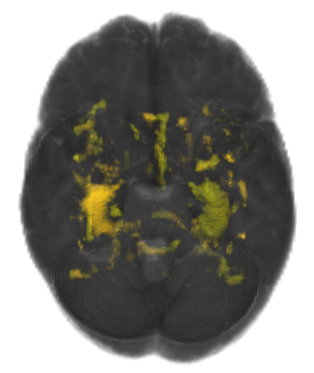

Refer to caption

Figure 3: Hippocampus

The hippocampus is a component of human brains responsible for committing short-term episodic and declarative memory into long-term memory, as well as navigation [29]. Hippocampus segmentation is important in the diagnosis of Alzheimer’s disease (AD), as it is one of the components first affected by the disease. A reduction in hippocampal volume can be used as a marker for AD diagnosis [30].

Humans have 2 hippocampi, shaped like seahorses, as shown in Figure 3. Our goal is to classify each voxel in an MR Image as non-hippocampus, left hippocampus, or right hippocampus. We are using this problem to evaluate different deep learning techniques for patch-based segmentation. All images are labeled by one human expert. Unfortunately, none of the images have been labeled by more than 1 human expert to determine variances in human labeling.